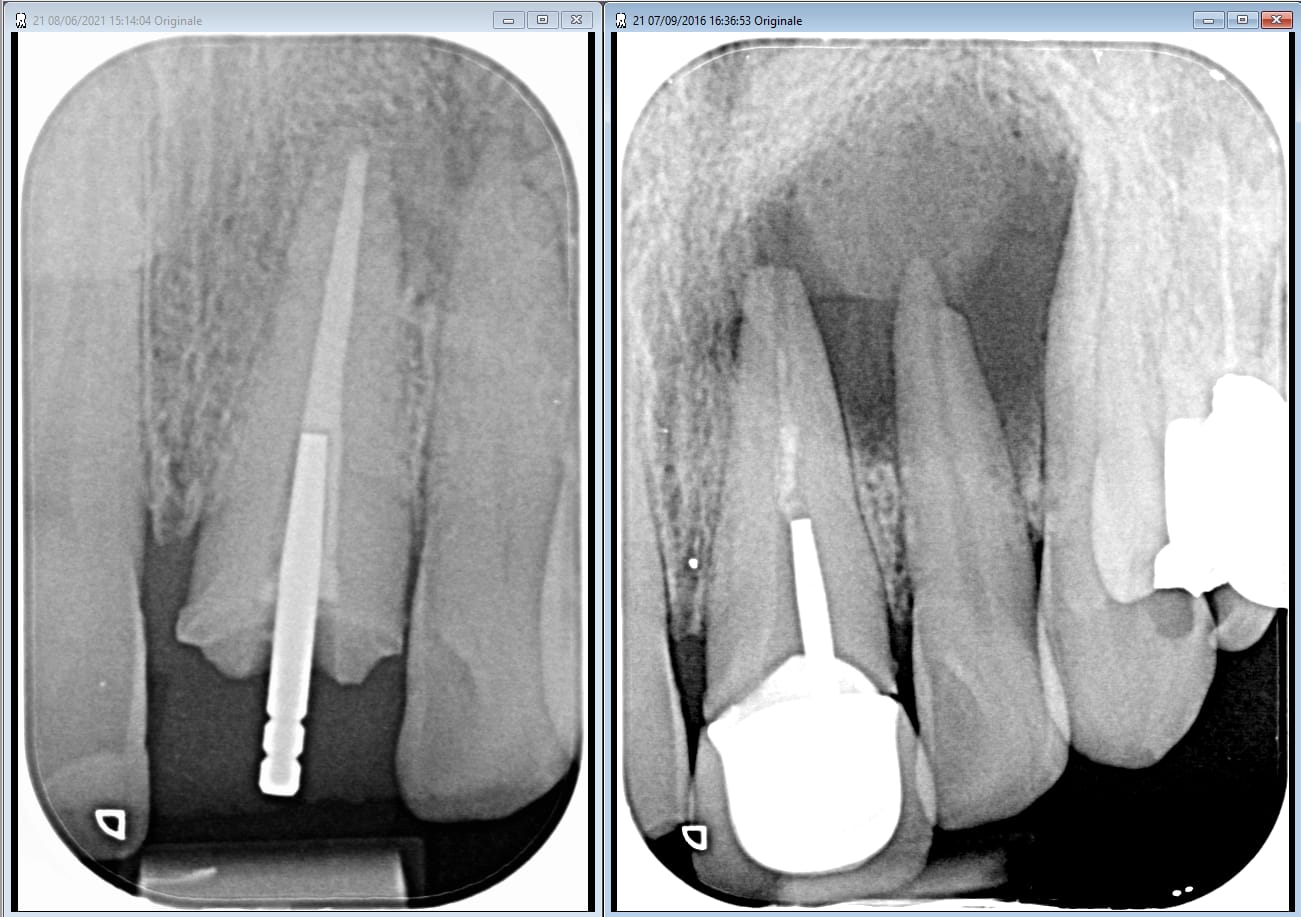

un revenant que j'ai vu mardi... la aussi j'ai pas mis la digue... je crois que son ancien dentiste n a pas de crachoir.

La provisoire qui tient 5 ans a 60e c'est super rentable ;)

Qualitay oer4ln - Eugenol